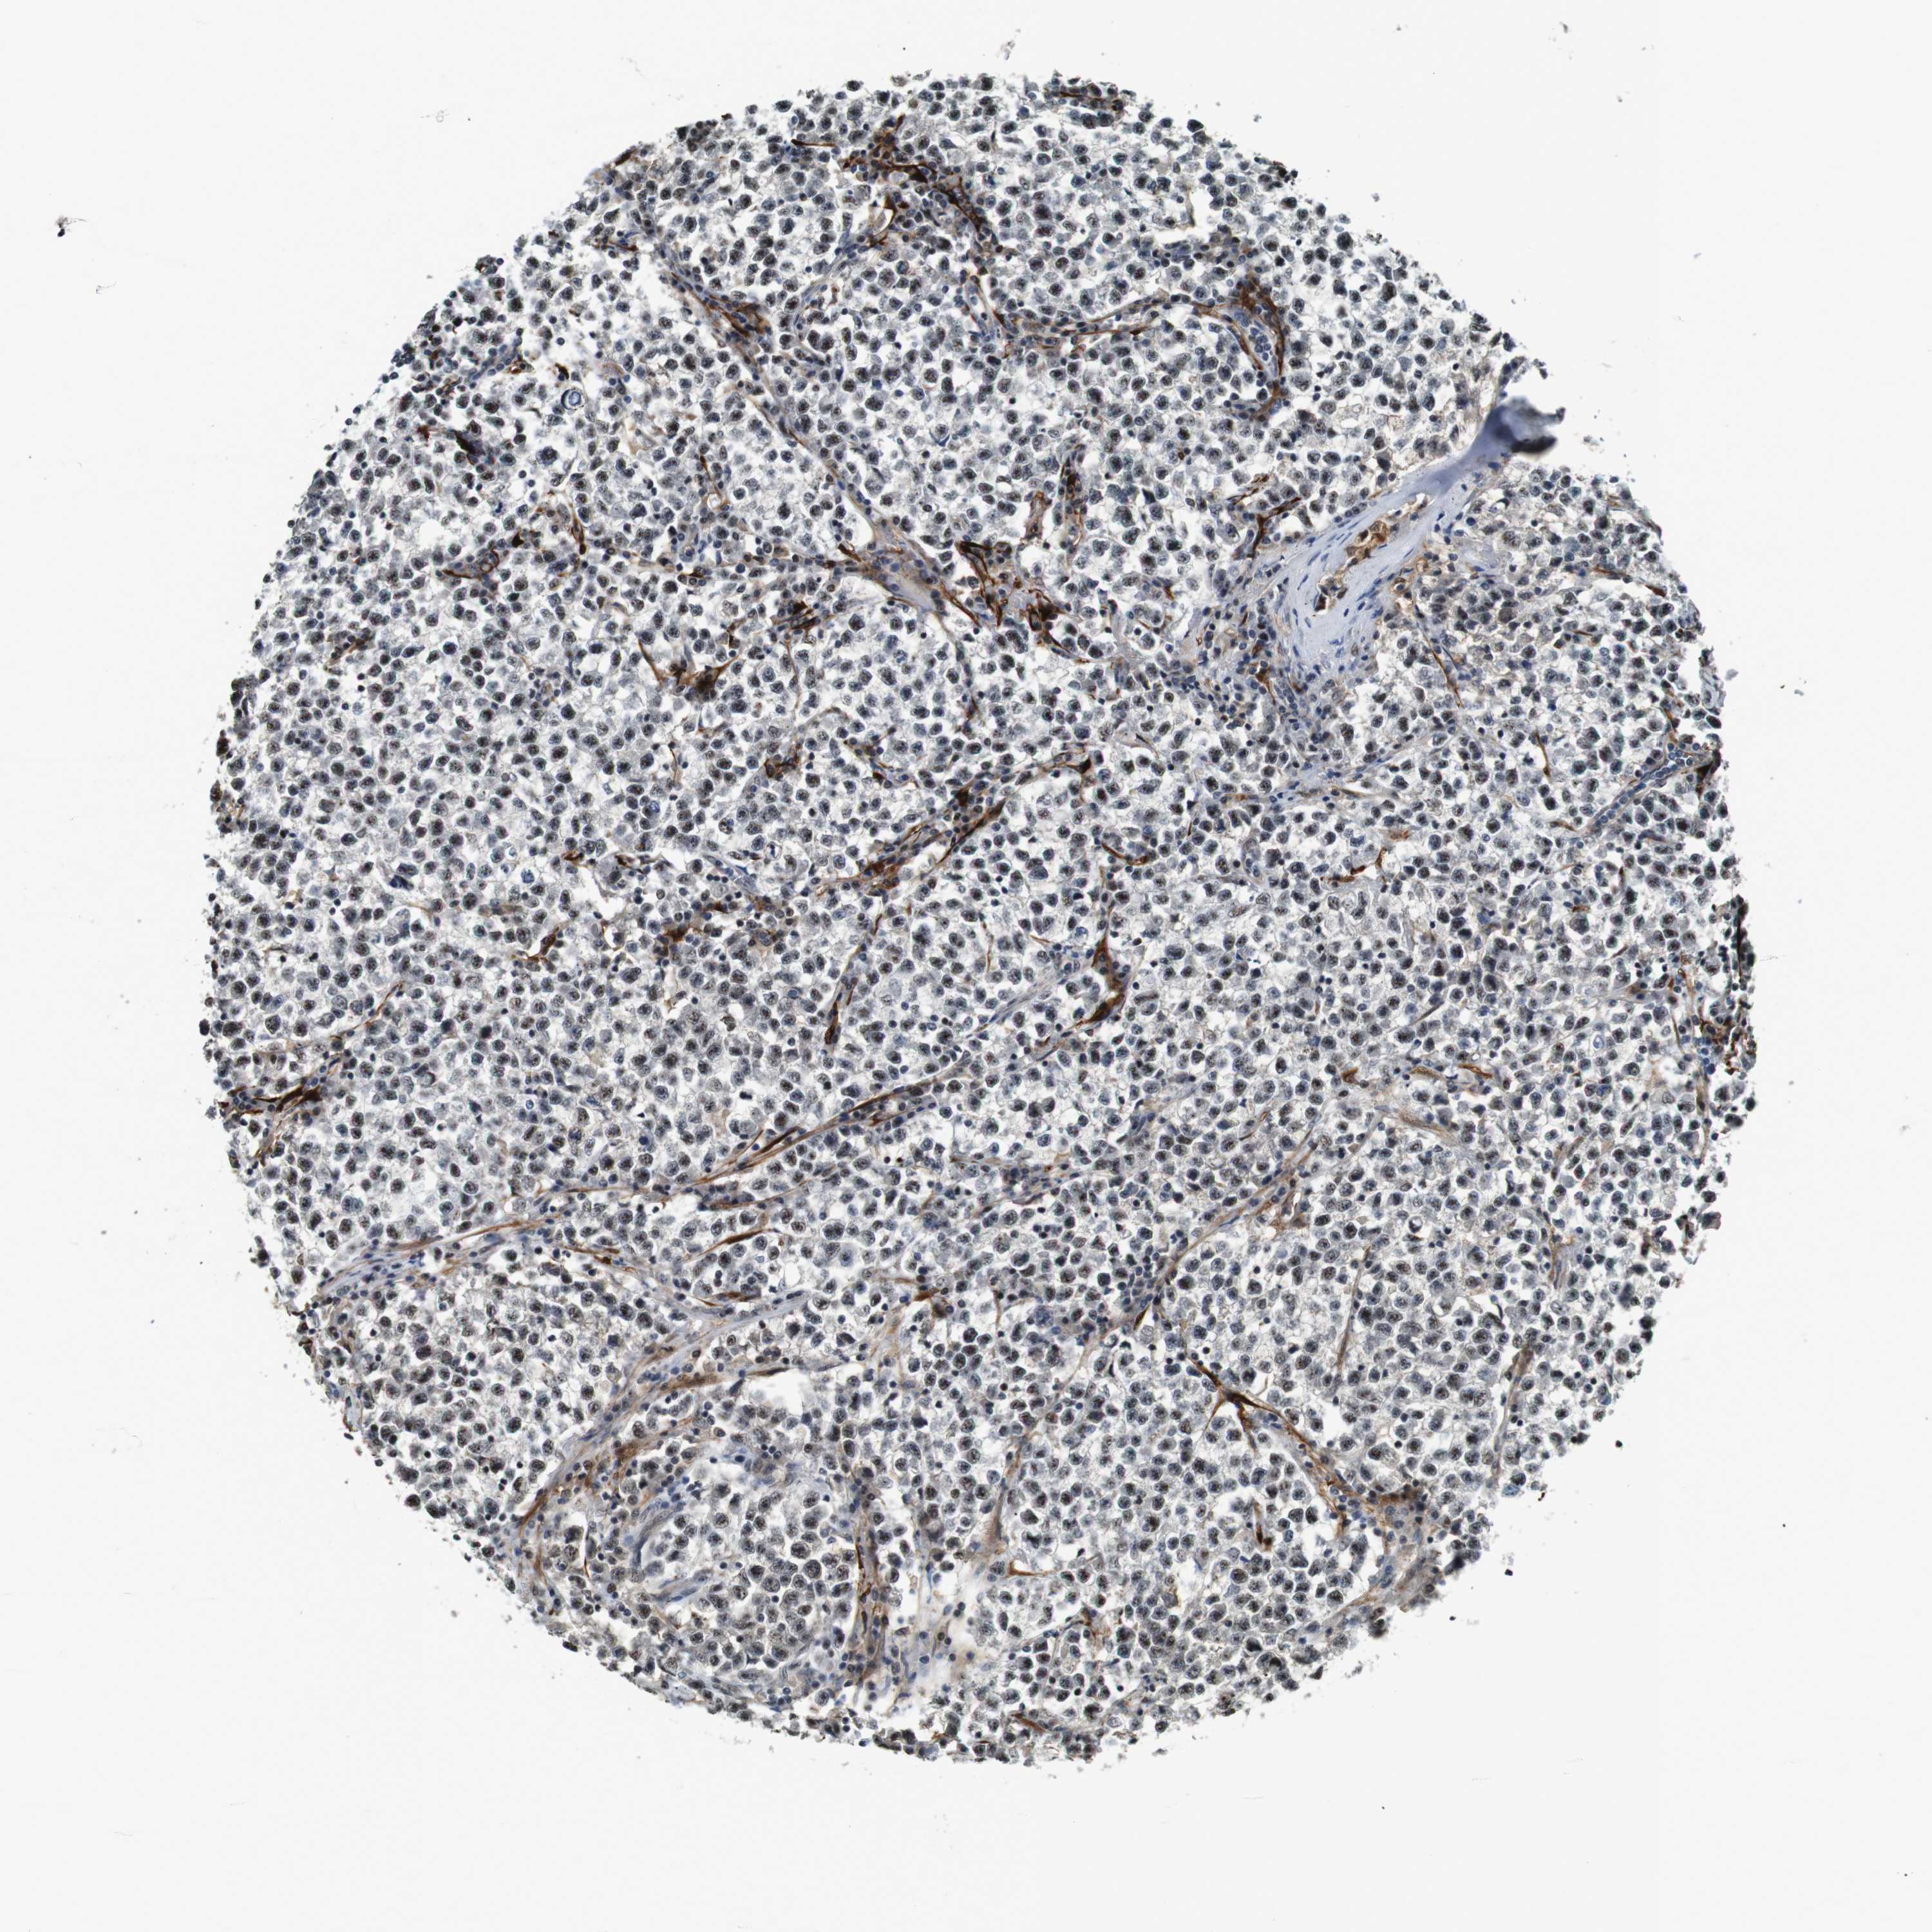

TESTIS CANCER - Protein expressioni

A mouse-over function shows sample information and annotation data. Click on an image to view it in a full screen mode. Samples can be filtered based on level of antibody staining by selecting one or several of the following categories: high, medium, low and not detected. The assay and annotation is described here.

Note that samples used for immunohistochemistry by the Human Protein Atlas do not correspond to samples in the TCGA dataset.

Antibody stainingi

Antibody staining in the annotated cell types in the current human tissue is reported as not detected, low, medium, or high, based on conventional immunohistochemistry profiling in selected tissues. This score is based on the combination of the staining intensity and fraction of stained cells.

Each image is clickable and will lead to virtual microscopy that enables deeper exploration of all samples and also displays staining intensity scores, fraction scores and subcellular localization as well as patient and tissue information for each sample.

Antibody HPA014179

Carcinoma, Embryonal, NOS

Seminoma, NOS